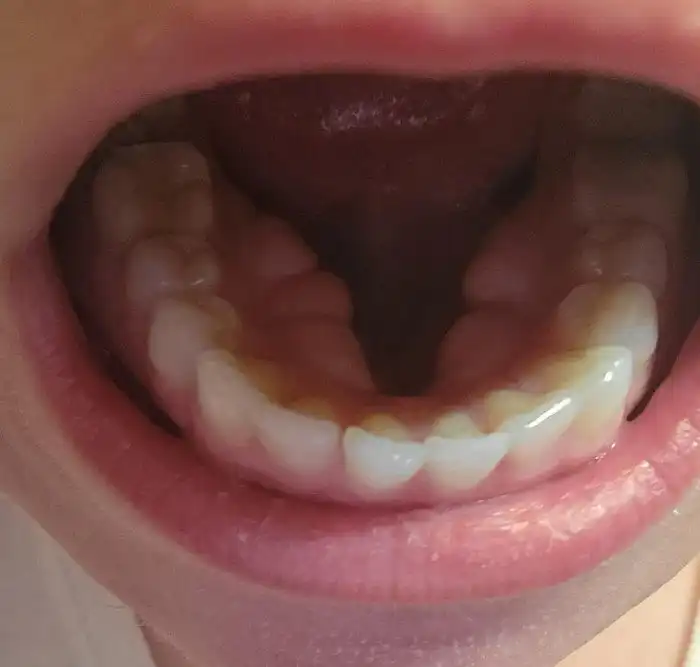

"У меня на нёбе начал расти зуб. Сегодня его удалили"